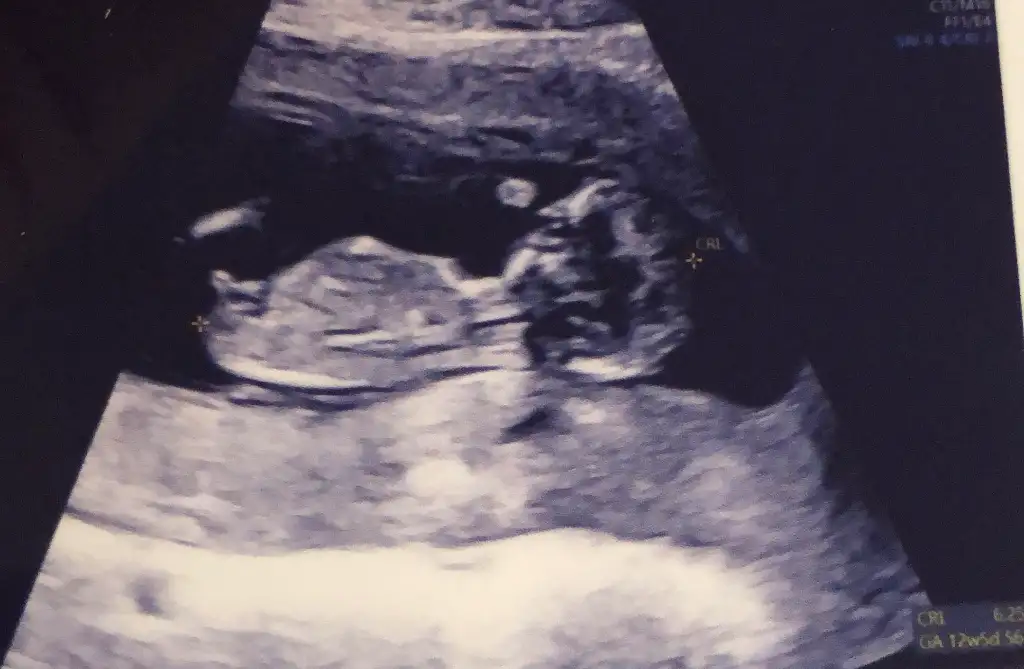

Yapılan hiçbir iyilik ve kötülük maalesef unutulmuyor. Bu zamanlar da çok başkaymış. Daha doğmadan insan üstüne titriyor bir şey olmasın diye. Annelik daha şimdiden böyleyken herkesin çoook anlayışlı olması lazım. Allah iyi insanlarla karşılaştırsın. Kötü insanlara fırsat vermesin inşallahBöyle zamanlar unutulmuyor işte iyi olanda kötü olanda. Sevindim senin adına bayram öncesi bi kaç gün grip gibi oldum çünkü ilaçta almayınca zor cidden neyseki çabul geçti. Evet evet şimdiden söylemek lazım umarım dikkat ederler o zaman hepimizin çevresine anlayışlı insanlar olur umarım![]()